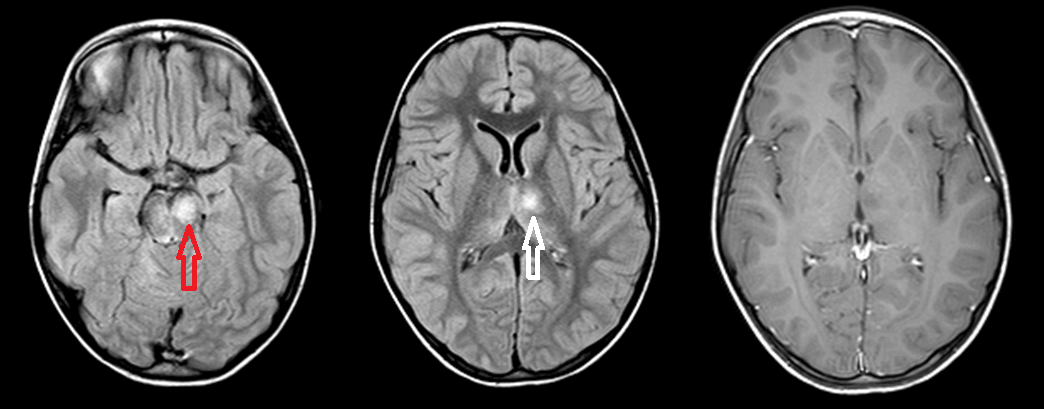

Figure: Axial FLAIR at the level of the midbrain (A) and the thalamus (B) demonstrate increased signal in the left anteromedial thalamus (red arrow) and ventral midbrain (white arrow). Axial postcontrast T1 demonstrates no enhancement of the thalamic signal abnormality (the midbrain abnormality also did not enhance but is not shown).

Unlike MS, ADEM does not typically involve the calloseptal interface (the inferior surface of the corpus callosum immediately adjacent to the septum) and it often involves the deep grey matter (thalamus, basal ganglia, dentate etc).